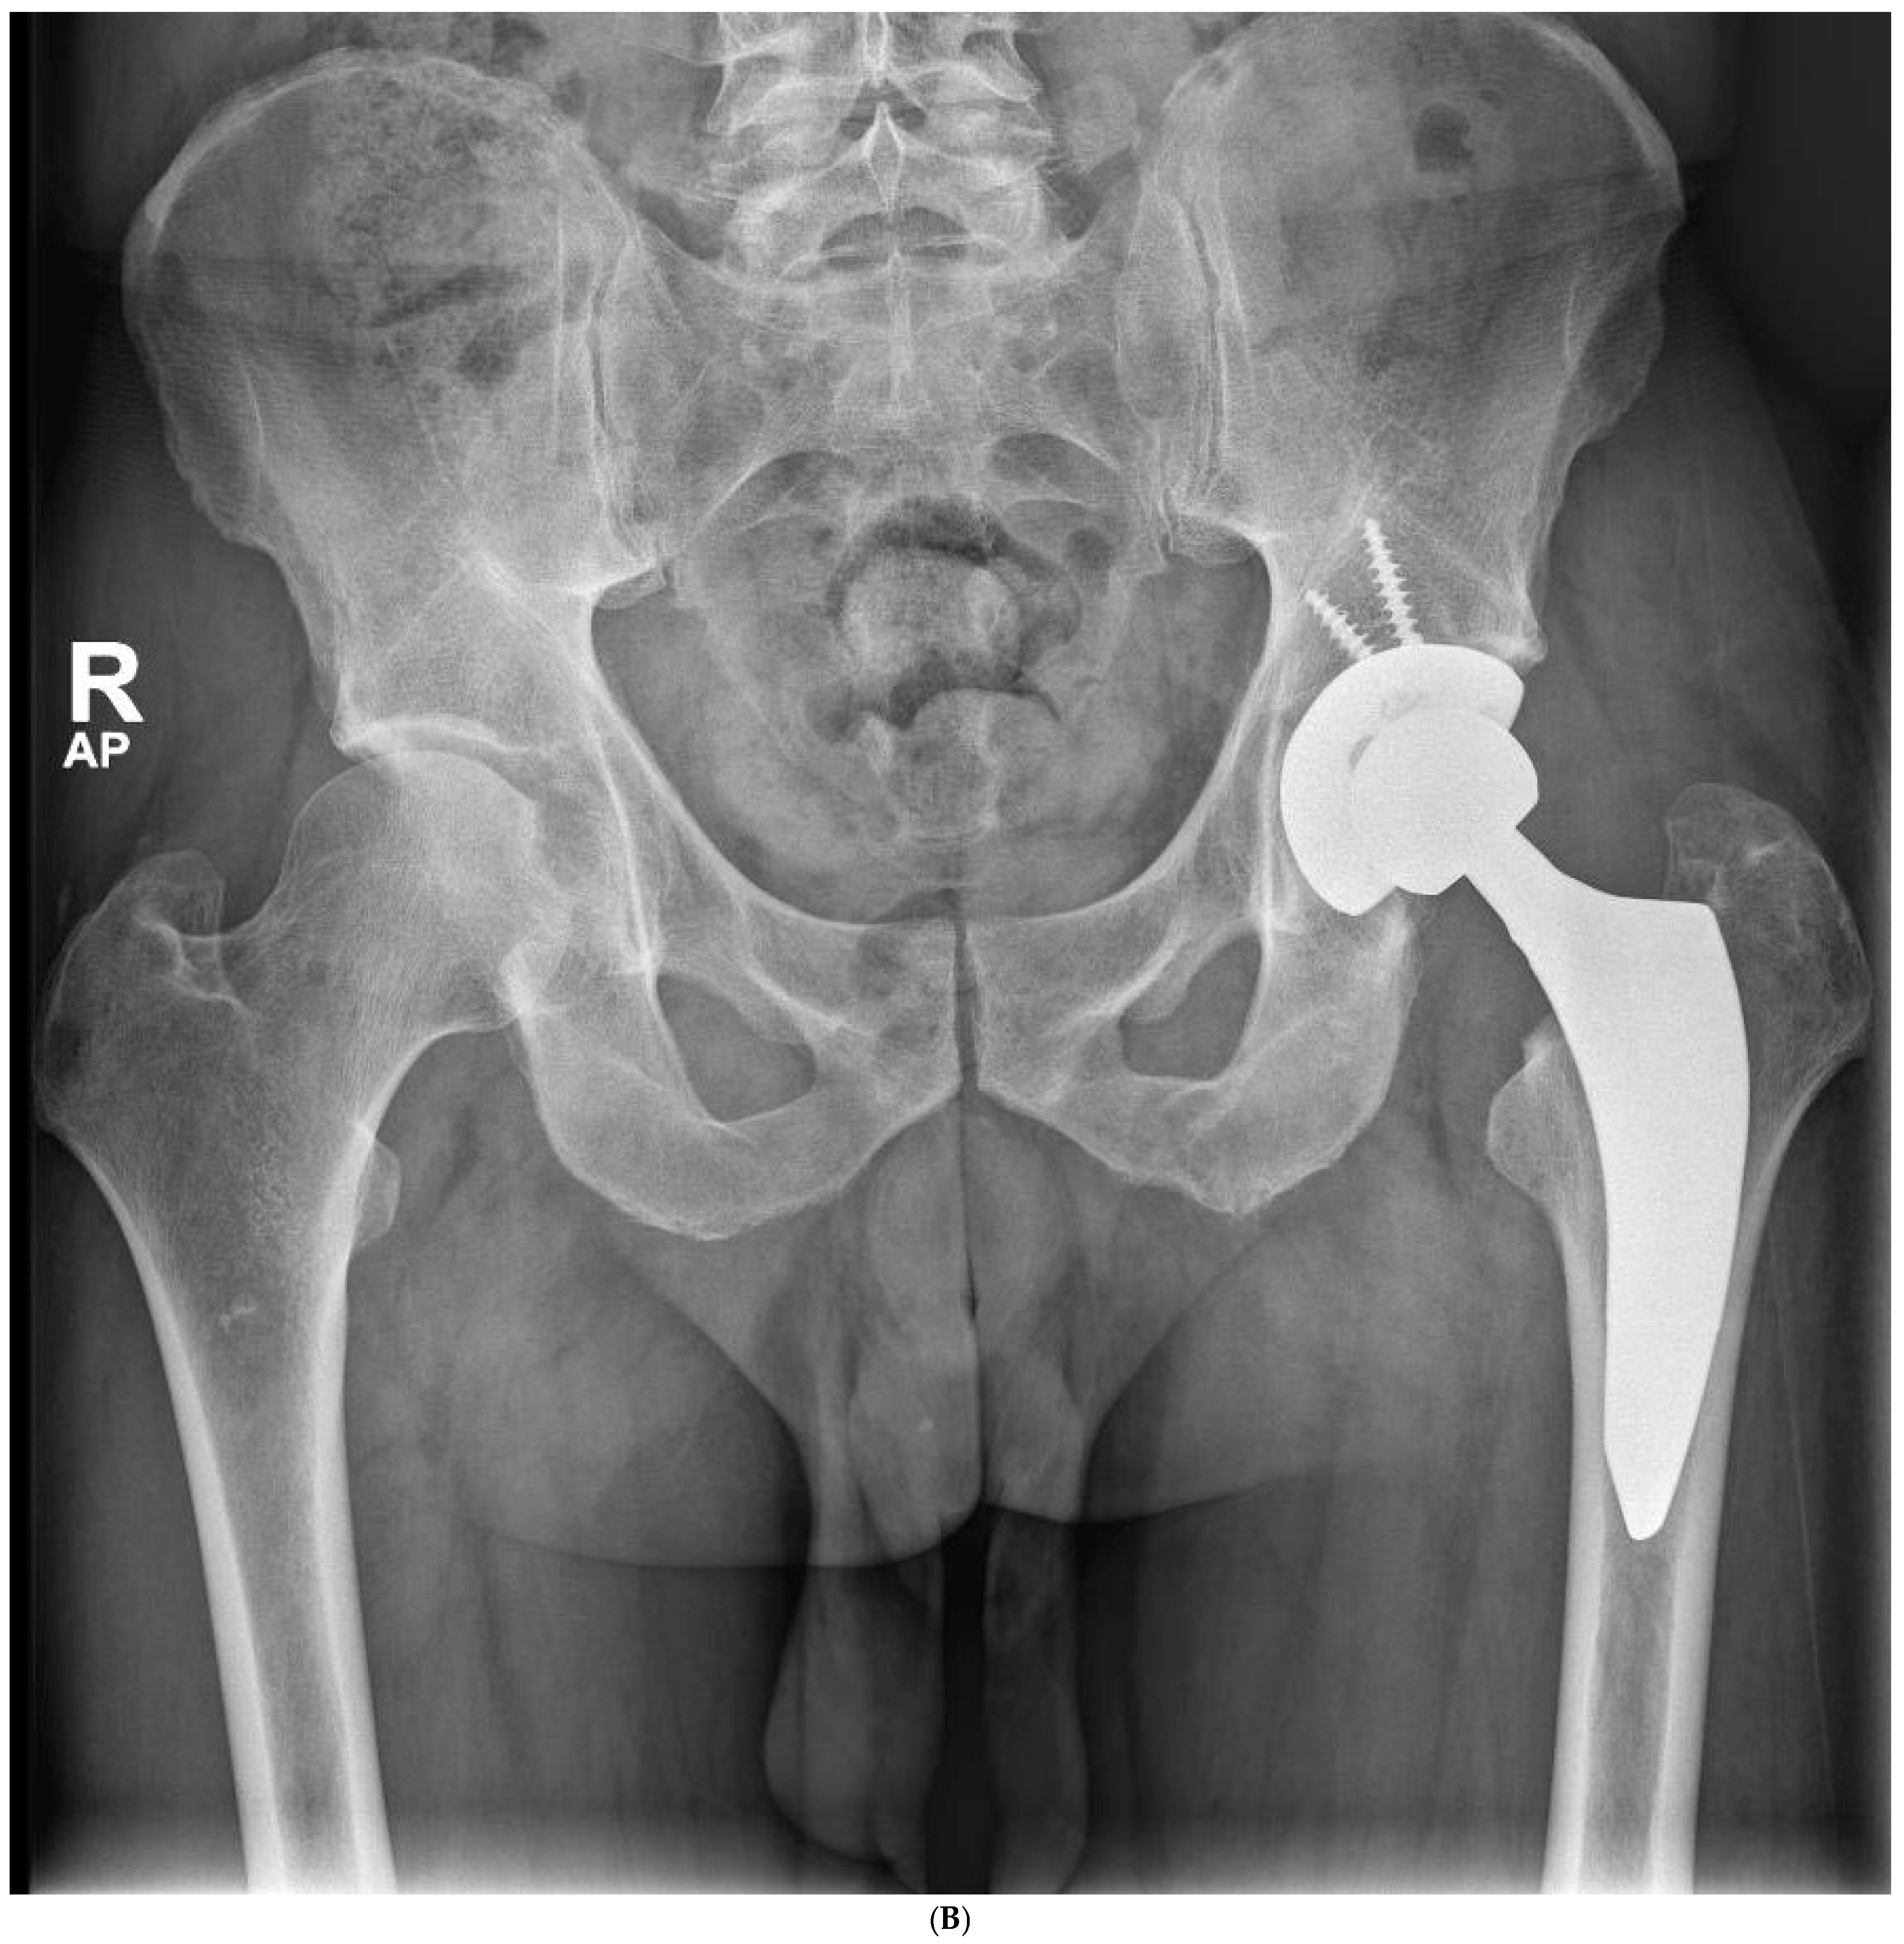

Figure 4.

(A) Preoperative anteroposterior X-ray. Left hip sustained a displaced femoral neck fracture. (B) Postoperative anteroposterior X-ray (CSS group). Femoral stem shows osseointegration and good proximal loading, with no bone resorption at final follow-up. (C) Postoperative lateral X-ray (CSS group). At final follow-up, the stem shows no subsidence and good fixation.